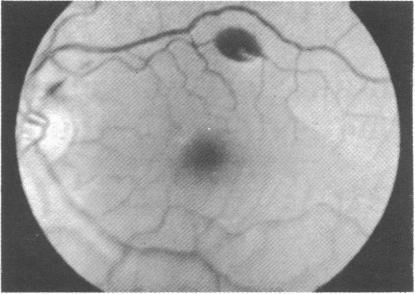

During the 1975 British Everest Expedition, which made the first ascent of the south-west face, observations were made in relation to mountain sickness and the appearance of retinal changes. Two Sherpas with cerebral oedema and one Briton with pulmonary oedema were treated. Retinal haemorrhages occurred in four out of six Britons who were newcomers to altitudes over 6000 m (19 685 ft) but in only two out of 14 Britons who had previously visited these altitudes. Intraocular pressures during ascent to 6000 m were within normal limits. The relevance of the ocular findings to acclimatisation in previous years was examined, the results supporting the hypothesis of a "carry-over" effect from previous visits to high altitude.

在1975年英国珠穆朗玛峰探险队首次从西南面登顶期间,对高山病和视网膜变化的出现进行了观察。两名患有脑水肿的夏尔巴人和一名患有肺水肿的英国人接受了治疗。在6名初到海拔超过6000米(19685英尺)高度的英国人中,有4人出现视网膜出血,但在之前曾到访过这些高度的14名英国人中,只有2人出现视网膜出血。在上升到6000米的过程中,眼压在正常范围内。研究了这些眼部检查结果与前几年适应过程的相关性,结果支持了前次前往高海拔地区存在“延续”效应的假说。